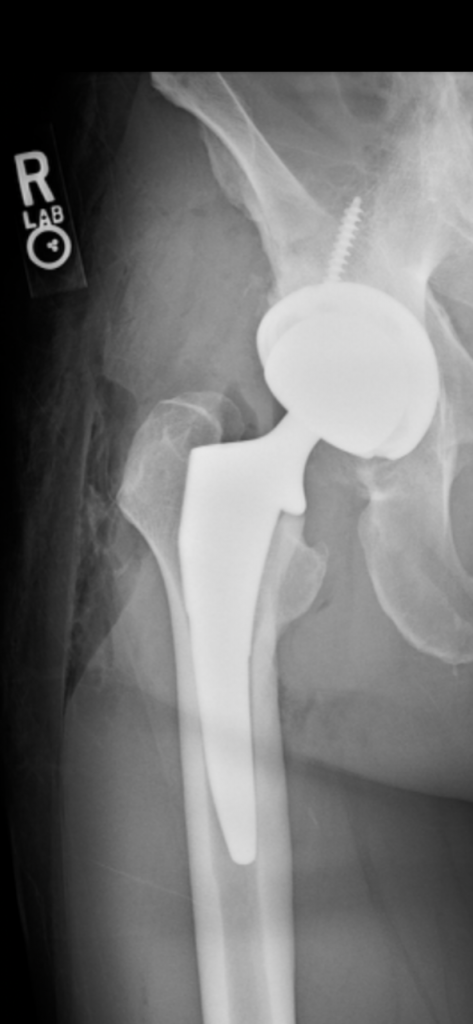

Minimally-invasive hip replacement

Patient-specific hip replacement

Same-day discharge (outpatient) hip replacement

Robotic hip replacement

Dr. Vigdorchik focuses on safe and correct surgical techniques. Many errors in joint replacement are completely avoidable, which is why Dr. Vigdorchik creates a customized patient-specific 3-dimensional surgical plan (basically virtually doing the surgery before ever entering the operating room) and then uses a robot or computer-assisted technology to execute that plan. That way, he can ensure the quickest recovery and improvement in quality of life, with the least amount of complications.